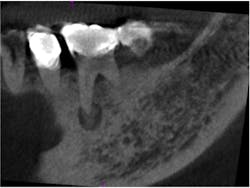

Fig. 2 is a sagittal slice through the lesion, further showing the mixed nature of the lesion. Figs. 3 and 4 are coronal and axial slices respectively. Both coronal and axial slices show that the PDL is intact around the root end and show that the lesion has caused erosion of the buccal cortical plate. Due to the unusual appearance of this lesion, an oral and maxillofacial radiologist also evaluated the CBCT scan.

Fig. 2: Sagittal slice through the lesion associated with tooth No. 30. Note the mixed appearance of the lesion. Note that the PDL can still be seen around the mesial root.